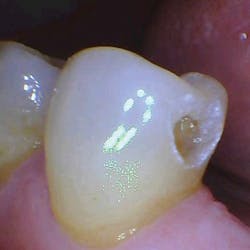

With the help of magnification, we are able to prepare small Class II lesions without sacrificing the marginal ridge, ensuring the longevity of our restoration and maximizing the remaining tooth structure with this minimally invasive approach (figures 3a–3d).

Figures 3a–3d: Minimally invasive Class II preparation with marginal ridge preservation